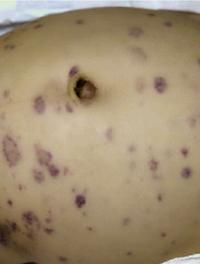

Le papillome inversé est une tumeur bénigne des fosses nasales qui se caractérise par la prolifération de cellules épithéliales en amas (papillome) vers le chorion sous-jacent : cette particularité est à l’origine du vocable inversé. Cliniquement, il entraîne le plus souvent une obstruction nasale unilatérale avec rhinorrhée. Le bilan complémentaire nécessite une IRM centrée sur les cavités sinusiennes et une biopsie. Le traitement est chirurgical et consiste en l’exérèse [...]